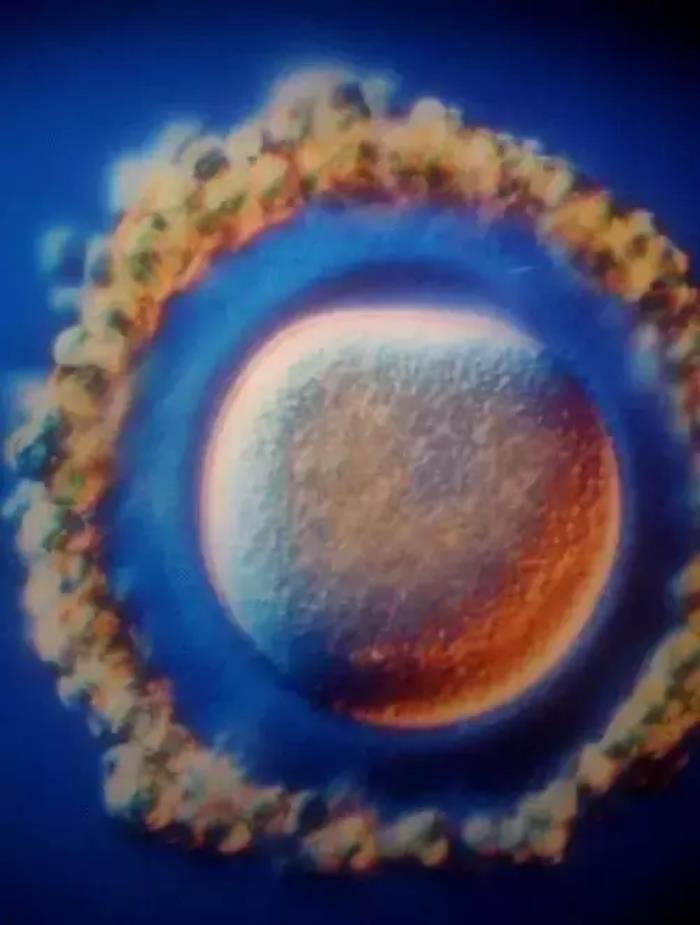

卵细胞

决定性的相遇

2亿精子中只有一颗精子与卵子结合